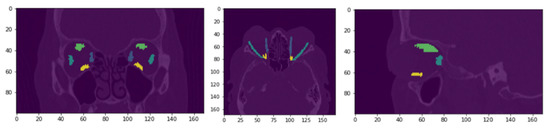

3.2. Qualitative Evaluation